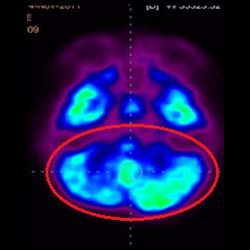

細(xì)胞治療前 PET CT 掃描顯示神經(jīng)組織中的藍(lán)/黑色區(qū)域,表明腦癱引起的大腦損傷。

腦癱細(xì)胞療法, 腦癱治療

細(xì)胞治療后,藍(lán)色和黑色區(qū)域減少,并且看到更活躍的區(qū)域。這表明損傷減少并改善了大腦功能。